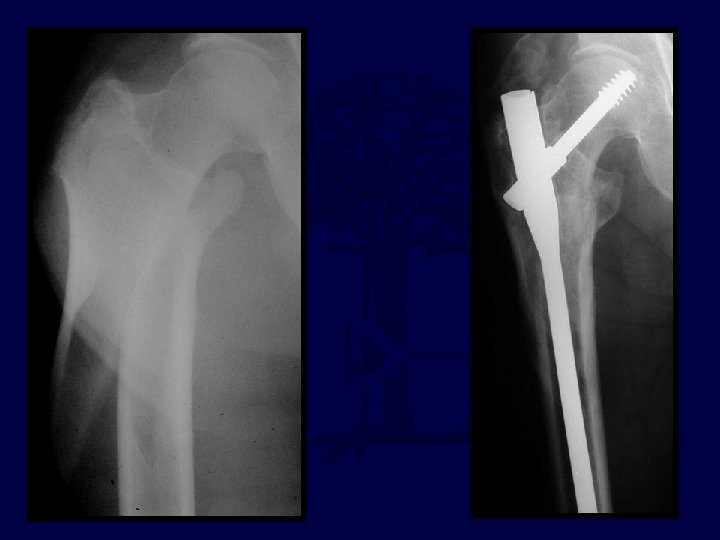

27 yo jogger struck by car, closed, isolated injury

27 yo jogger struck by car I’d reduce & fix with: A. 95° blade B. DCS plate C. “Recon” Nail D. DHS E. Intramedullary hip screw (PFN, TFN, IMHS, GAMMA)

A. The reduction is satisfactory B. The TAD is satisfactory C. Both are satisfactory D. Neither are satisfactory